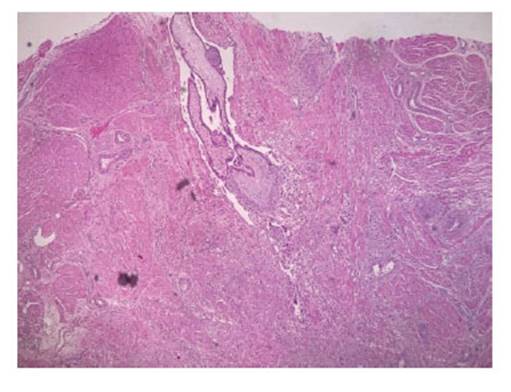

Due to persistent bleeding, decreased hemoglobin and satisfied parity, it was decided to perform a total abdominal hysterectomy. The specimen was sent for histopathological study. In the macroscopic description, an exophytic lesion was reported in the uterine fundus, irregular, hemorrhagic, with tortuous and congestive vessels, extending to the thickness of the underlying myometrium. In the microscopic description, the lesion described in the uterine fundus corresponded to numerous chorionic villi, some of them with hyaline changes, surrounded by trophoblastic cellular elements in direct contact with deep myometrial muscle fibers, without intervening decidual tissue. The final report concluded placental accreta (Figure 5). The patient had a favorable evolution and was discharged the day after surgery, clinically stable and asymptomatic. No wound healing problems were observed during the 3-month follow-up period.